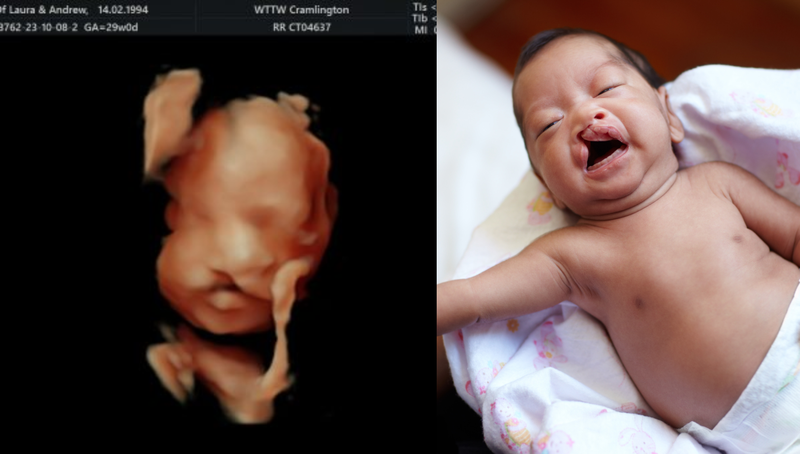

Hình ảnh siêu âm thai nhi bị hở hàm ếch thường cho thấy một khe hở ở môi trên hoặc vòm miệng. Trên siêu âm 2D, khe hở này có thể xuất hiện dưới dạng một đường đen giữa môi trên hoặc trong vòm miệng.

Siêu âm 3D và 4D cung cấp hình ảnh chi tiết hơn, giúp bác sĩ quan sát rõ ràng cấu trúc khuôn mặt của thai nhi và xác định mức độ nghiêm trọng của dị tật. Việc sử dụng siêu âm 3D có thể giúp phát hiện khe hở môi sớm hơn và cung cấp hình ảnh rõ ràng hơn về cấu trúc khuôn mặt của thai nhi.

Hình ảnh siêu âm thai nhi bị hở hàm ếch cung cấp thông tin quan trọng giúp cha mẹ và bác sĩ chuẩn bị cho việc chăm sóc và điều trị sau sinh. Việc phát hiện sớm dị tật này qua siêu âm, đặc biệt là với sự hỗ trợ của công nghệ 3D và 4D, đóng vai trò then chốt trong việc đảm bảo sức khỏe và chất lượng cuộc sống cho trẻ. Do đó, việc thực hiện siêu âm định kỳ và tuân thủ các hướng dẫn của bác sĩ trong suốt thai kỳ là vô cùng quan trọng.